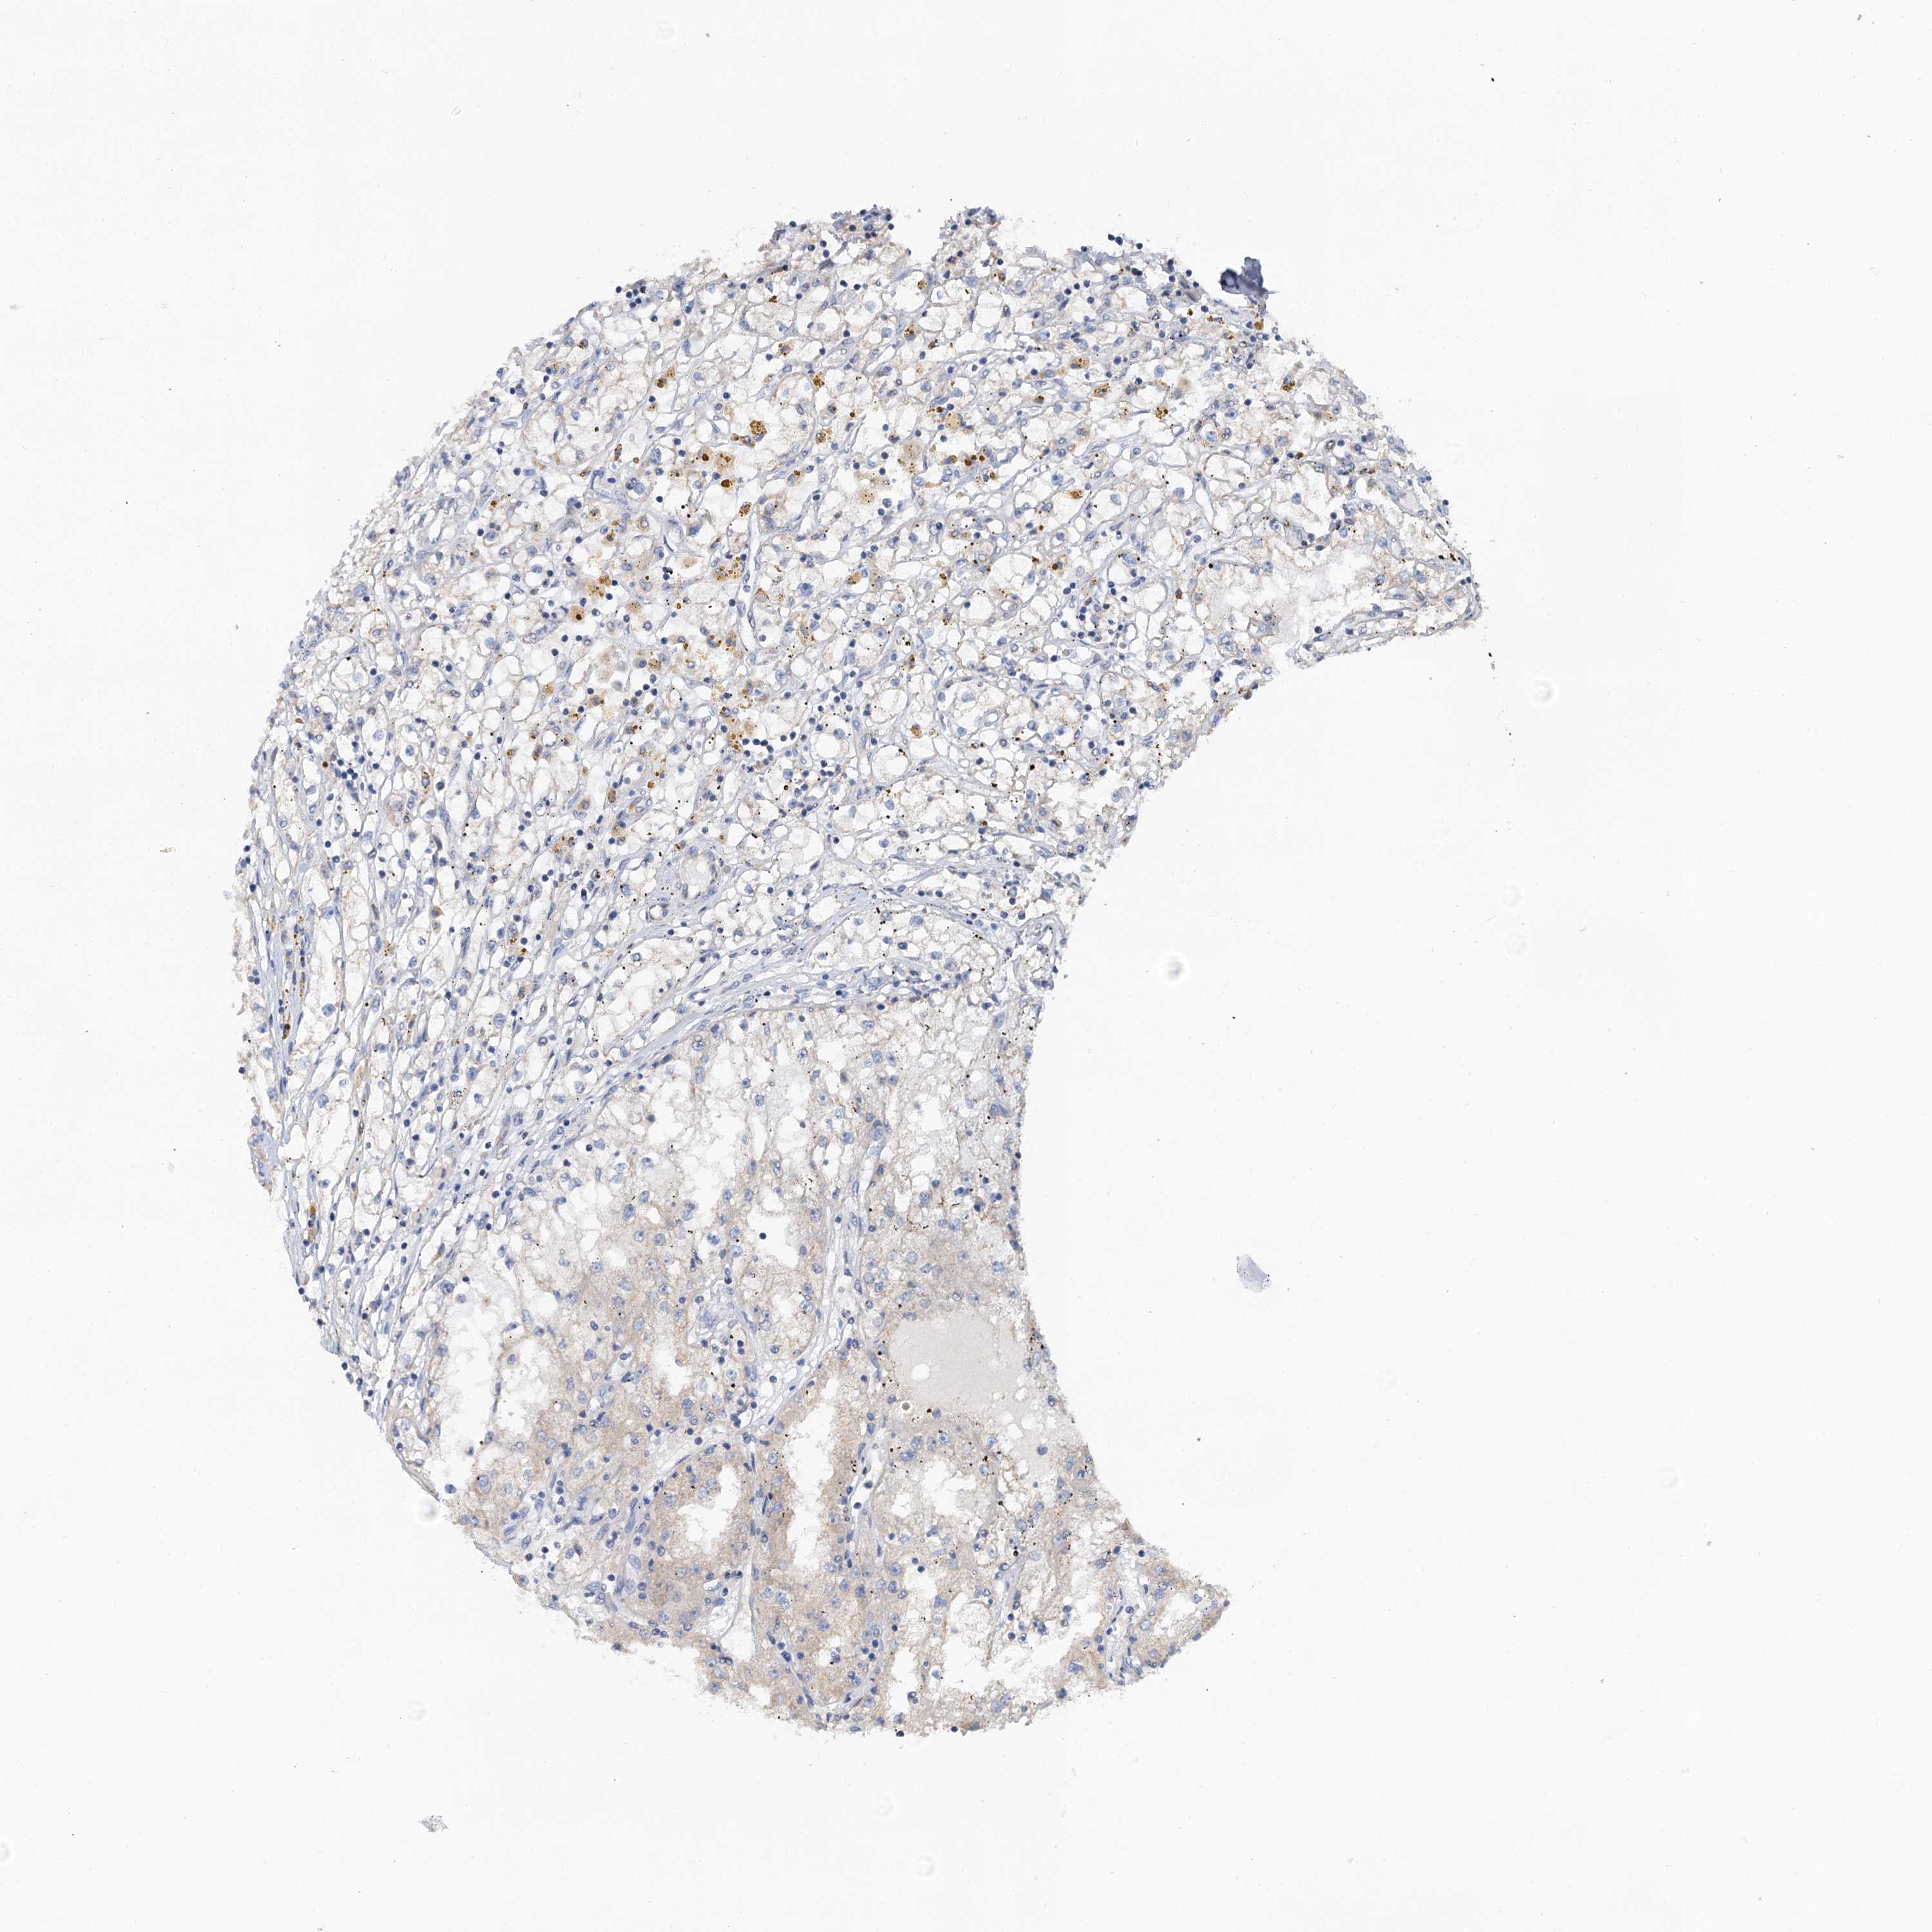

KIDNEY RENAL PAPILLARY CELL CARCINOMA (TCGA) - Interactive survival scatter ploti

The Survival Scatter plot shows the clinical status (i.e. dead or alive) for all individuals in the patient cohort, based on the same data that underlies the corresponding Kaplan-Meier plots. Patients that are alive at last time for follow-up are shown in blue and patients who have died during the study are shown in red.

The x-axis shows the expression levels (FPKM) of the investigated gene in the tumor tissue at the time of diagnosis. The y-axis shows the follow-up time after diagnosis (years). Both axes are complimented with kernel density curves demonstrating the data density over the axes. The top density plot shows the expression levels (FPKM) distribution among dead (red) and alive patients (blue). The right density plot shows the data density of the survived years of dead patients with high and low expression levels respectively, stratified using the cutoff indicated by the vertical dashed line through the Survival Scatter plot. This cutoff is automatically defined based on the FPKM cutoff that minimizes the p-score. The cutoff can be changed by dragging the vertical line or by entering a cutoff value in the square labeled "Current cut-off".

Under the Survival Scatter plot the p-score landscape (black curve; left axis) is shown together with dead median separation (red curve; right axis). Dead median separation is the difference in median mRNA expression between patients who have died with high and low expression, respectively. It is calculated as follows: median FPKM expression of dead patients with high expression - median FPKM expression of dead patients with low expression. This is intended to aid the user in visually exploring custom cutoffs and the associated p-scores and dead median separation.

Individual patient data is displayed and can be filtered by clicking on one or more of the category buttons on the top of the page. Categories describing expression level and patient information include: high, low, alive, dead, female, male and tumor stages. The scale of the x-axis can be toggled between linear and log-scale by clicking on the "x log" button. Mouse-over function shows TCGA ID, patient information and mRNA expression (FPKM) for each patient.

& Survival analysisi

Kaplan-Meier plots summarize results from analysis of correlation between mRNA expression level and patient survival. Patients were divided based on level of expression into one of the two groups "low" (under cut off) or "high" (over cut off). X-axis shows time for survival (years) and y-axis shows the probability of survival, where 1.0 corresponds to 100 percent.

PLLP is not prognostic in Kidney Renal Papillary Cell Carcinoma (TCGA)